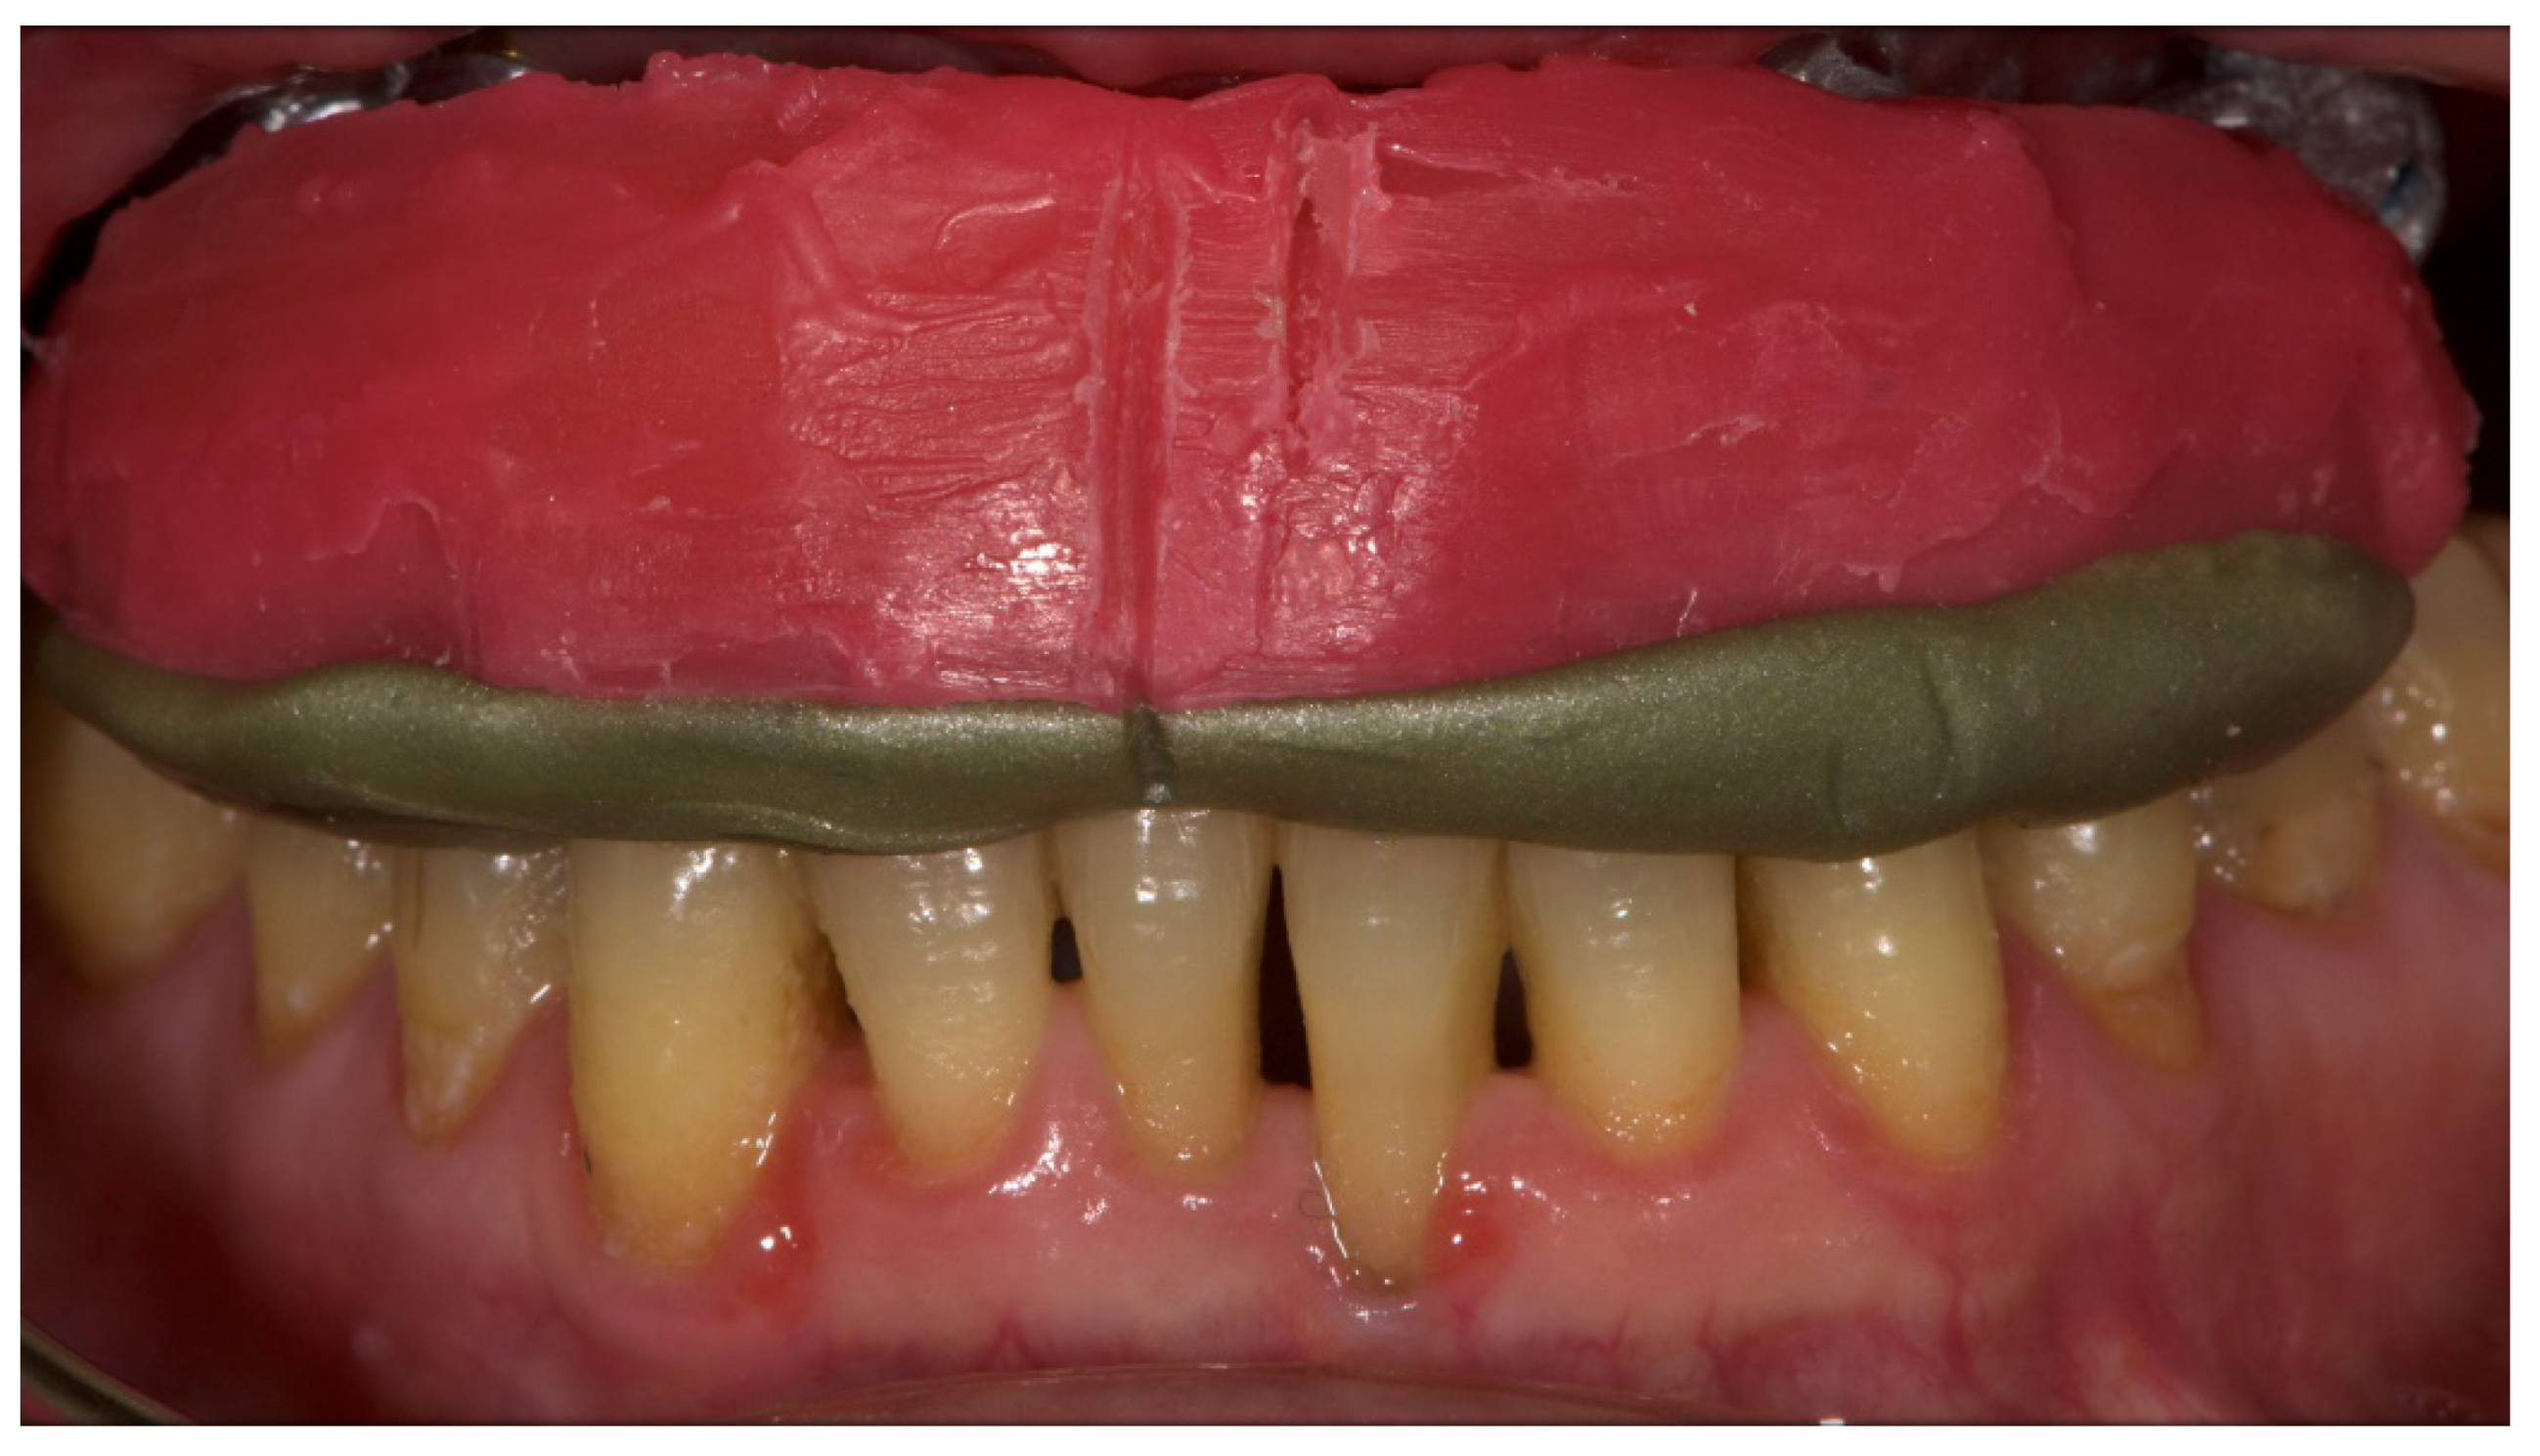

Figure 10.

Vertical dimension of occlusion.